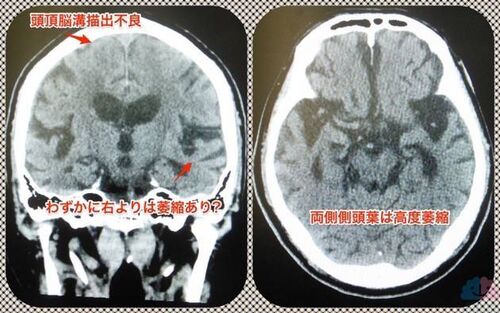

情報がほとんどない状態で治療を依頼されることの難しさ。

かかりつけ医からの情報提供書はない。入居先施設からの情報提供書やスタッフ同伴もない。あるのはお薬手帳と家族の嘆きのみ。 「それでも何とかして下さい」という依頼を受けることがある。